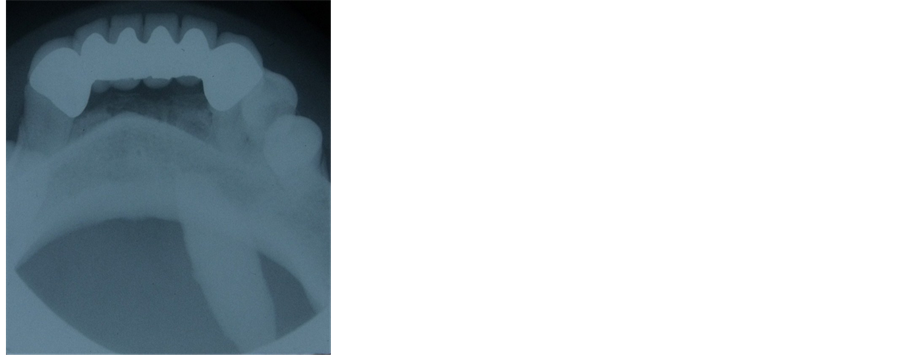

Extraoral examination revealed a palpable left submandibular gland and intraoral examination noted a large, firm and mild-tender swelling in the left anterior floor of the mouth in the region of the submandibular duct. Panoramic and occlusal radiographs were obtained for radiographical examination. Panoramic radiograph show- ed a large radioopaque mass superimposed on the left canine and premolar areas. A lower occlusal radiograph showed the large radioopaque mass in the left Wharton Duct (Figure 2, Figure 3)

Figure 3. Lower occlusal radiograph showing the sialolith.